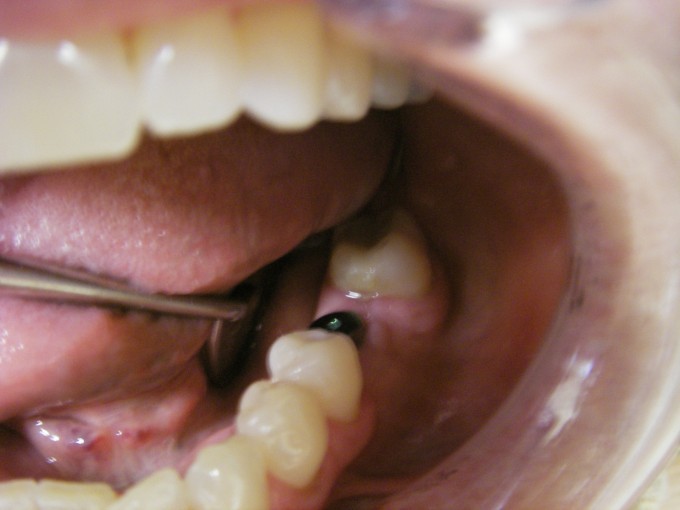

Implants

The titanium implant itself is below the gumline and fused to the bone already in this case. The metal substructure you see is the healing abutment. It is removed and an impression is made to then fabricate a tooth that fits the space to be replaced. In this case, the implant crown was screwed down to an abutment vs cemented.